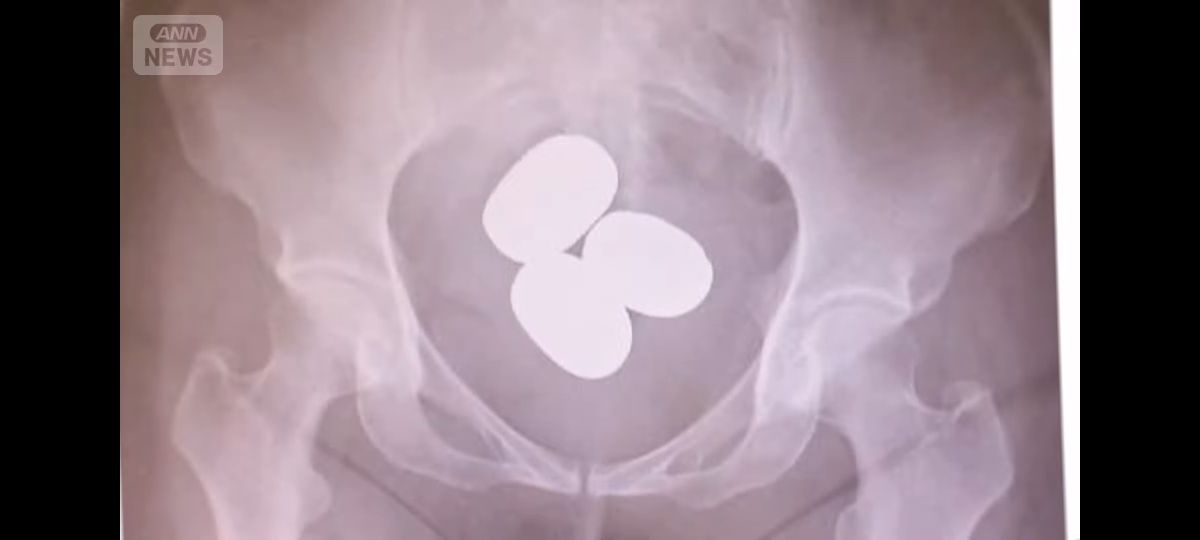

- 成田税関によりますと、今年1月から3月までに成田空港で航空機の乗客による金の密輸を33件、およそ46キロを摘発したということです。

そのうち、30件は金を粉状にして密輸していました。

量はおよそ45キロ、12億円相当です。30件のうち22人が女で、粉状の金は避妊具などに入れて体の中に隠す手口で持ち込まれていました。

- レントゲン写真卵みたい